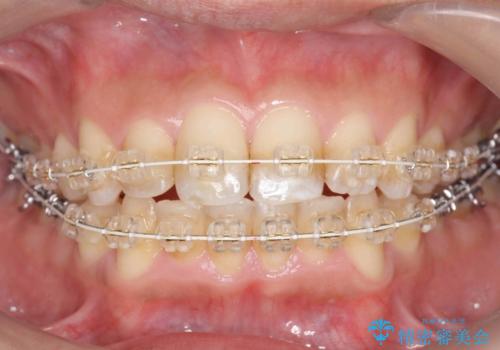

歯を抜かない矯正 奥歯のすれ違い咬合 下の八重歯

- 20代男性

- 矯正装置

- 審美装置

- 前歯のガタガタを主訴に来院。

奥歯はすれ違ってしまっていました。

口元も出ておらず、非抜歯を希望されたため、IPR(歯を削る処置)でスペースを確保しました。